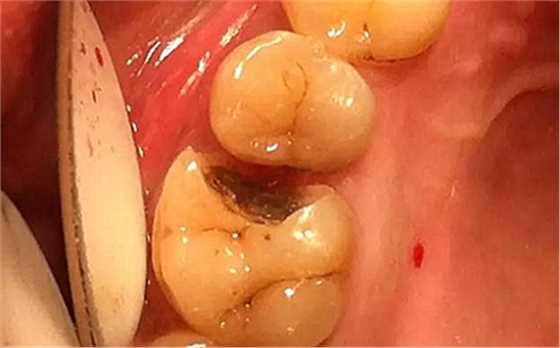

患者男性,35歲,B6銀汞充填后食物嵌塞,要求重新充填,口內(nèi)檢查見B6近中鄰頜面銀汞充填物,局部缺損,有繼發(fā)齲,去除原充填物及繼發(fā)齲,發(fā)現(xiàn)齲壞位于牙齦下方,給予冠延長手術(shù),同期嵌體預(yù)備,后一次性取模。(同樣設(shè)計為齦上邊緣)

硅橡膠取模后,灌注模型,科爾琥珀樹脂制作嵌體。